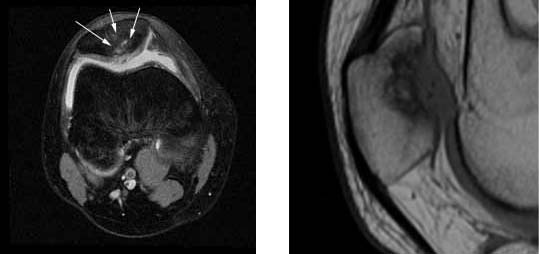

1. These are radiographs of her knee showing cystic areas in both the femur and the tibia (small arrows). These are consistent with a diagnosis of avascular necrosis which can be caused by high dose steroid medications used to treat leukemia.

2.Her MRI images demonstrate severe damage to the surface of the patellar cartilage as well as cystic degeneration within the bone (white arrows)